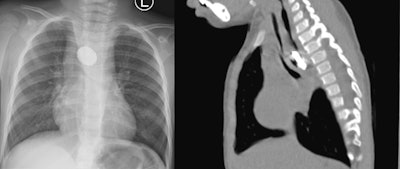

A chest x-ray revealed a halo sign and a thoracic CT scan showed a round object obstructing her esophagus. Attempts to visualize and retrieve the foreign body endoscopically were unsuccessful, and the surgeons performed a thoracotomy to retrieve it.